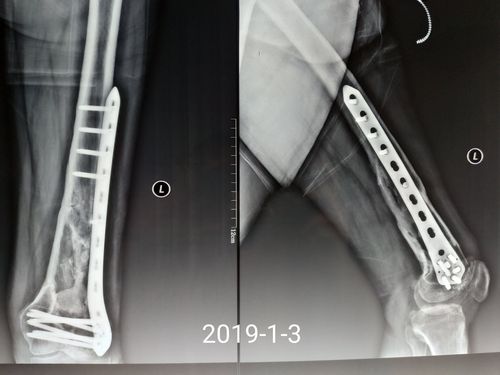

看这例股骨干骨折术后接下来将如何处理?

股骨干骨折不愈合次置骨换钉十钢板固定

股骨干骨折术后感染不愈合

股骨干骨折髓内钉图片